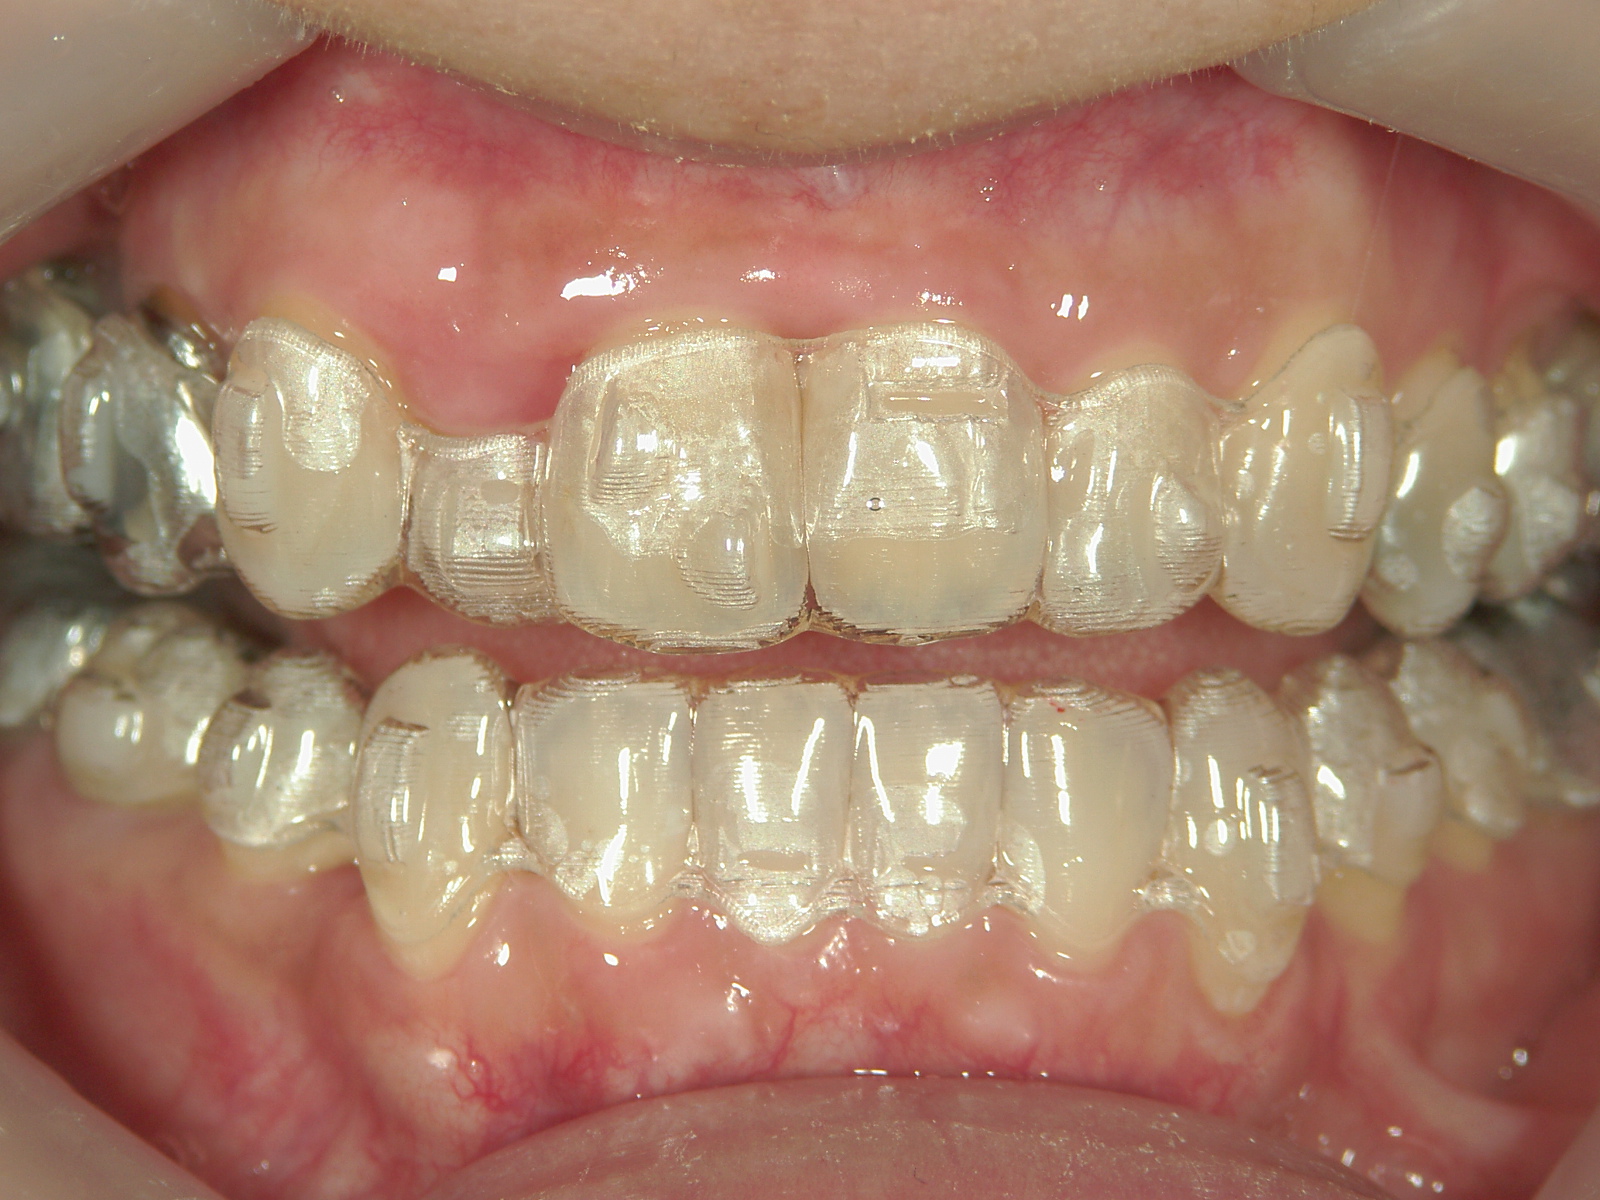

③矯正装置を除去し、インビザライン矯正で歯列を整えました。

①患者様はインビザライン矯正をご希望でしたが、上顎骨が小さく、受け口になっているので、インビザライン矯正で治療するために「骨切断OPE」「矯正装置(MSE+フェイスマスク)」で上顎骨を拡大しました。

②右上前歯が内側に入っているため、歯列に入る隙間を作るためにワイヤー矯正を併用し、右上前歯を出しました。